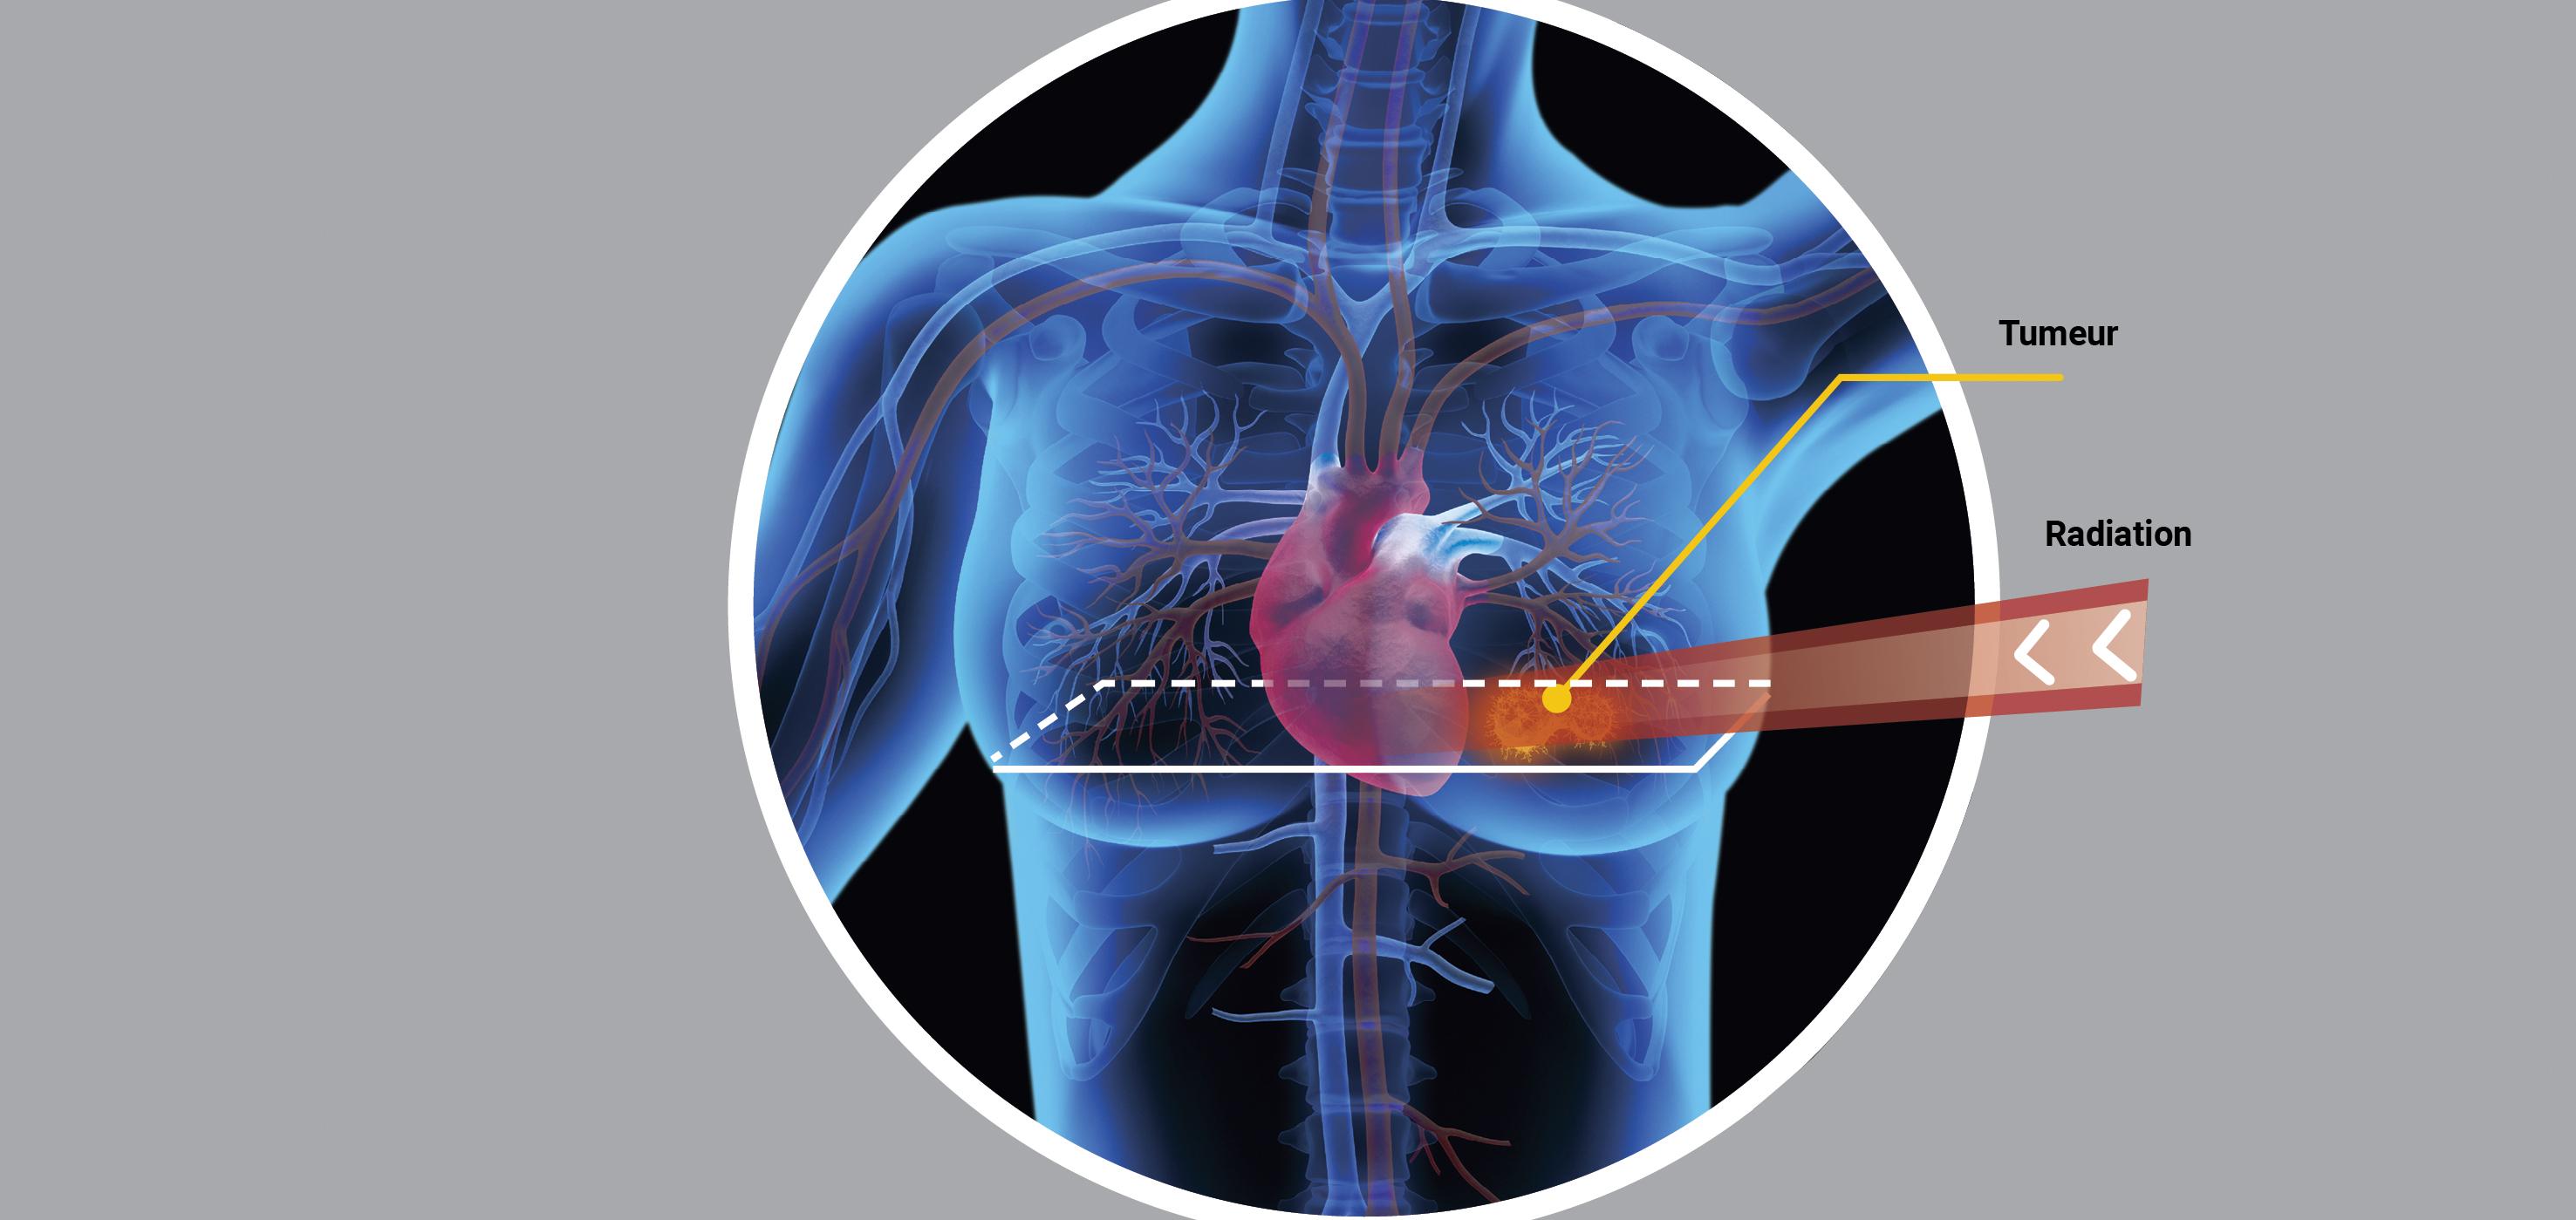

Utiliser des rayonnements ionisants pour attaquer une tumeur, voilà le principe de la radiothérapie (voir infographie "Radiothérapie : bienfaits et écueils"). « Plus de 50 % de patients atteints de cancer reçoivent une radiothérapie au cours du traitement de leur maladie. C’est le pilier principal de la lutte contre le cancer », rappelle Philippe Maingon, oncologue-radiothérapeute à l’hôpital de la Pitié-Salpêtrière à Paris. Et les techniques évoluent en permanence.

Lors d'une radiothérapie, la tumeur est irradiée par des rayonnements ionisants. Ceux-ci peuvent affecter le tissus sains avoisinants. Des recherches et des expertises contribuent à limiter ces dégâts.